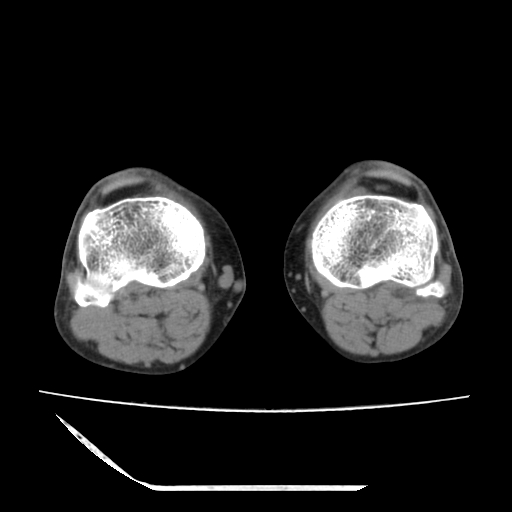

标题: CT13225:老年男性,左膝关节疼痛数月;请各位老师讨论。 [打印本页]

标题: CT13225:老年男性,左膝关节疼痛数月;请各位老师讨论。

骨质增生,骨性关节面硬化,关节积液,考虑退行性骨关节病

关节腔内少量积液,关节面退变。

双膝退变

骨质增生,骨性关节面硬化,关节间隙失常,关节积液,考虑退行性骨关节病.

这个病例诊断:退行性骨关节炎